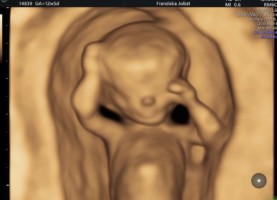

Ultraschalldiagnostik 12-14. SSW Erst-Trimesterscreening (NT-Mesung):

Das Ersttrimesterscreening ist eine differenzierte Ultraschalldiagnostik in der 12-14 SSW die ein ausführliches Organscreening und die Erfassung von sonografischen Chromosomenmarken, sowie eine Risikoberechnung aus Laborparamentern und Ultraschallmarkern beinhaltet. Diese Untersuchung ist keine Leistung der Krankenkassen und kann nur als IGEL-Leistung wahrgenommen werden

Mit Hilfe des Ersttrimesterscreenings (ETS) ist schon in der 12.-14. SSW durch die Beurteilung der Nackenfalte , des Nasenbeins und weiterer sonographischer Parameter (Ductus venosus, Trikuspidalklappe am Herzen etc.) sowie einer Blutentnahme (PAPP-A und freies ß HCG= plazentare Hormone) eine Risikoanalyse für das wahrscheinliche Auftreten einer Chromosomenstörungen Trisomie 21, Trisomie 13 oder Trisomie18 möglich. Die Erkennungsrate der Untersuchung beträgt ca.90-95% mit einer Falsch-Positiv-Rate von 2,5-5%.

Aufgrund des zusätzlichen ausführlichen Organscreenings können außerdem mit dieser Untersuchung Hinweise auf schwere organische Fehlbildungen frühzeitig erfasst werden. Nach Eingang der Laboruntersuchung wird eine für Ihre Schwangerschaft individuelle Risikoanalyse durchgeführt- das Ergebnis und damit das weitere Vorgehen entsprechend der Befunde wird mit Ihnen detailliert besprochen.

ETS- Bildergalerie